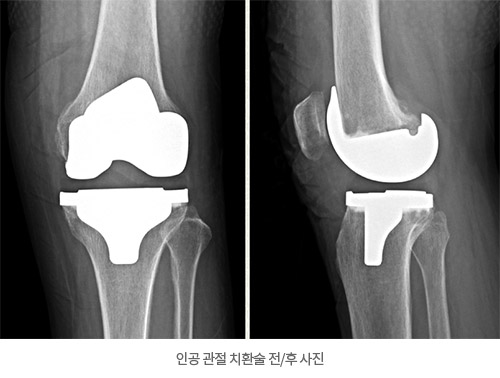

- └ 무릎 인공 관절 전치환술

무릎 인공 관절 전치환술